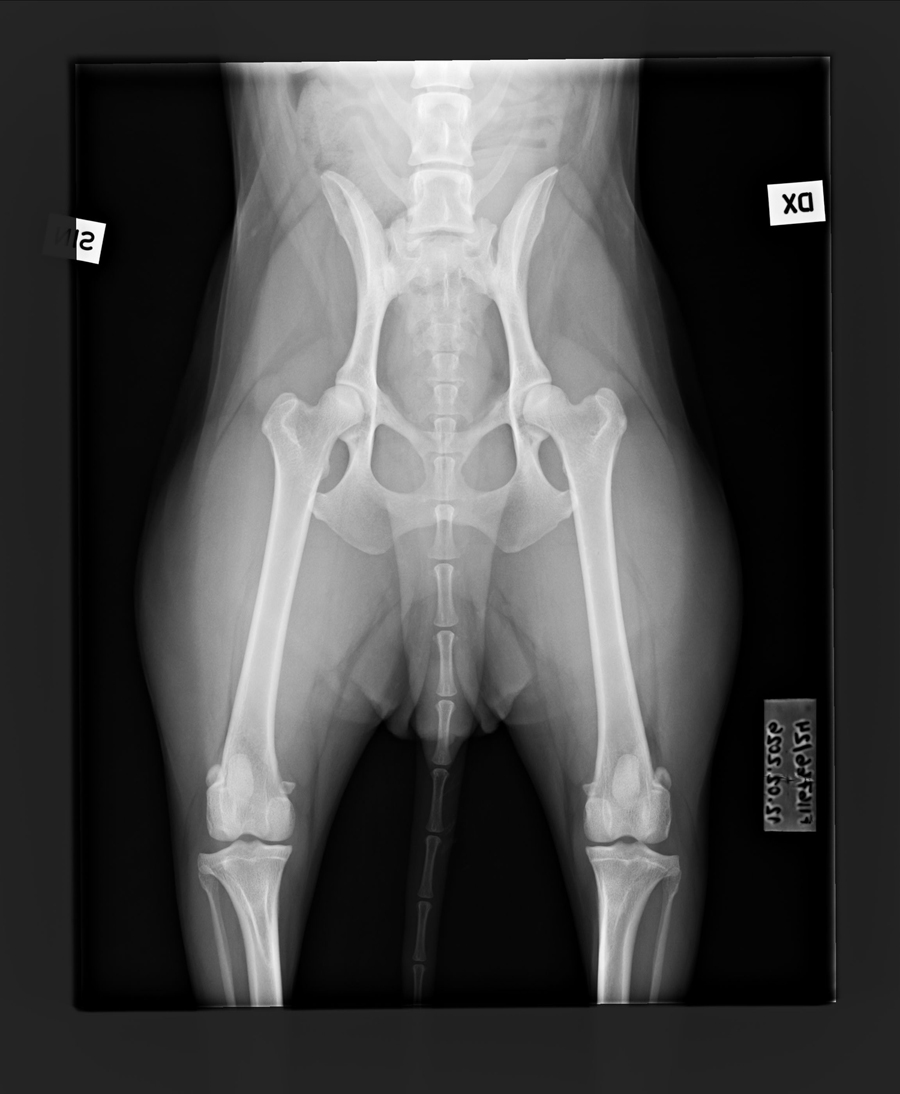

A/A |

0/0 |